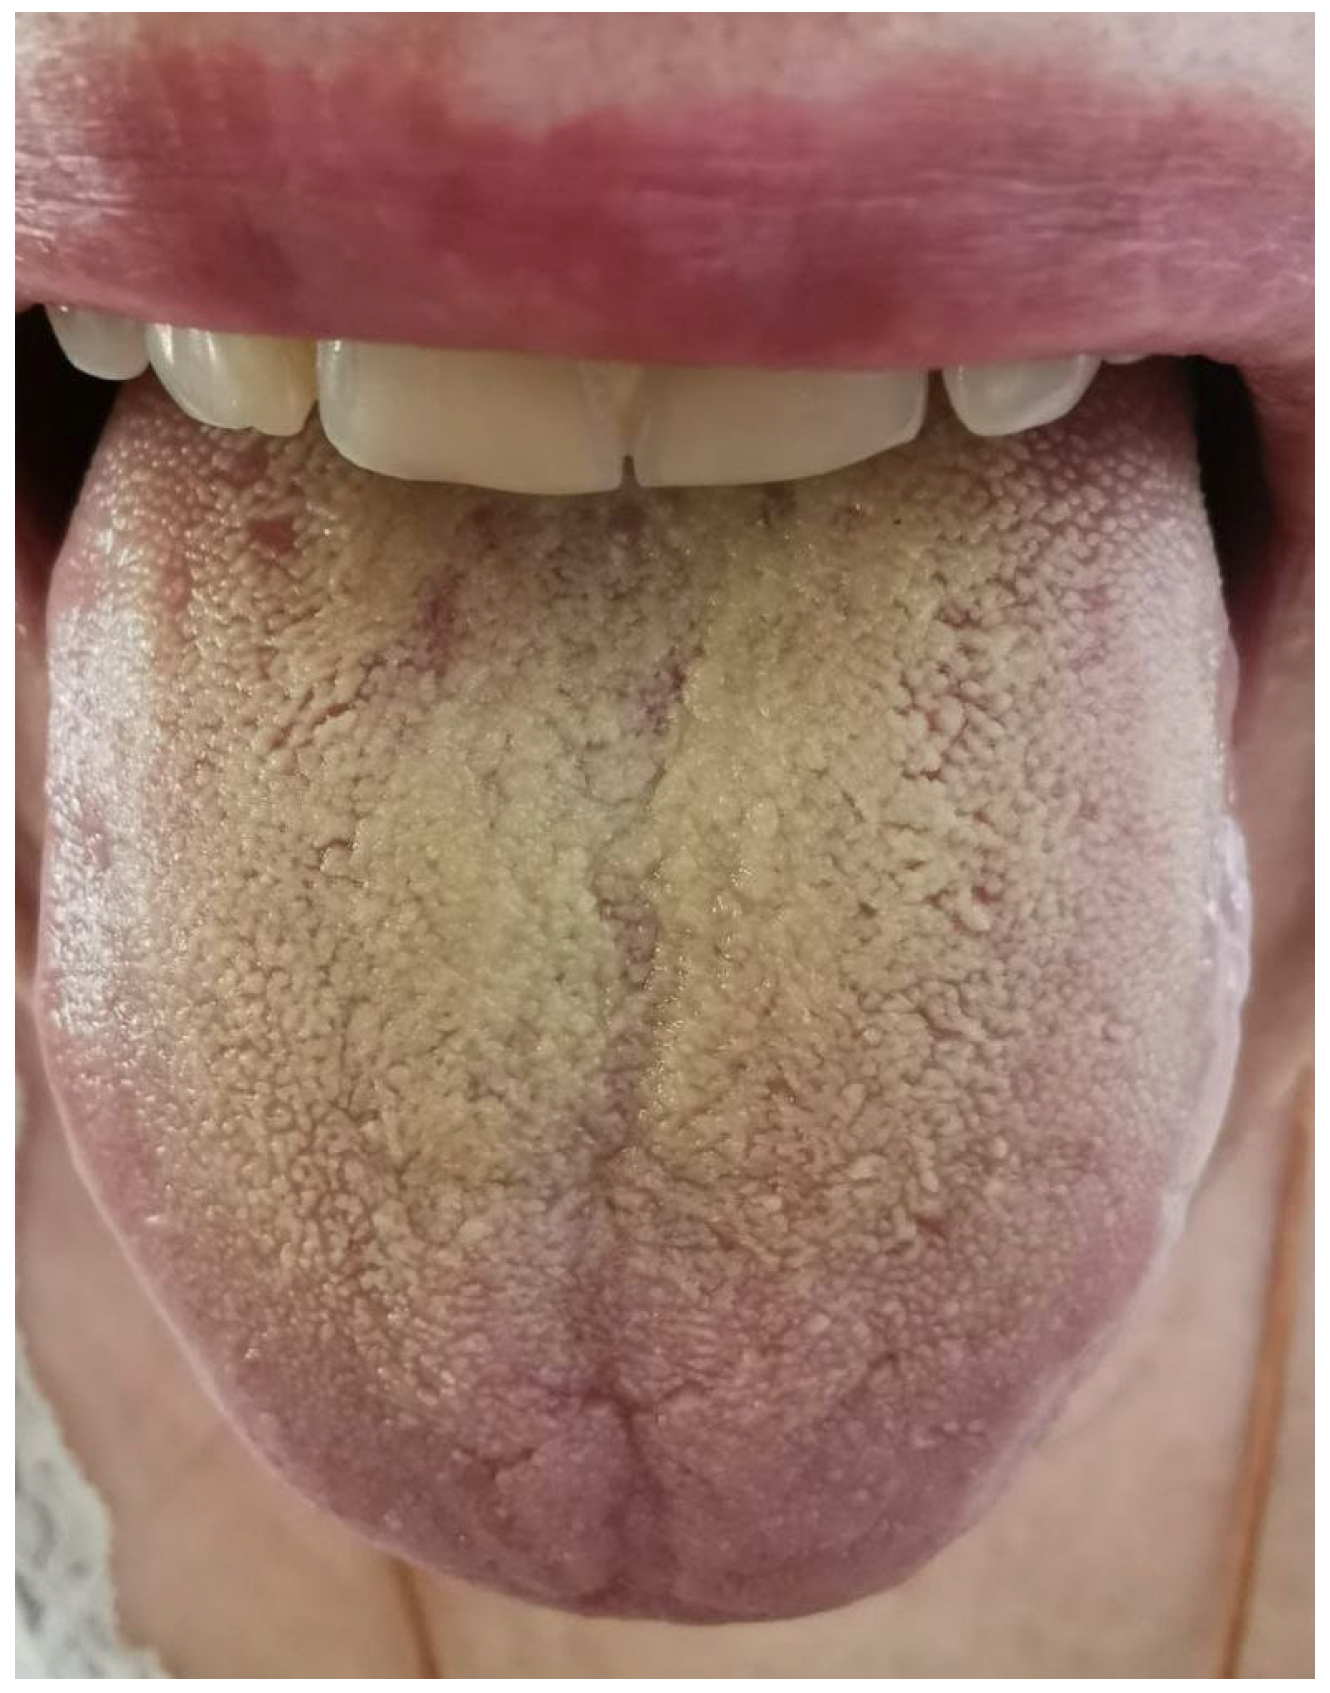

2.1. Results of Clinical Case Investigation

2.1.2. Results of Oral Microbiological Examination of Patient Sh. (Female, 52 Years Old)

4.1. Clinical Case